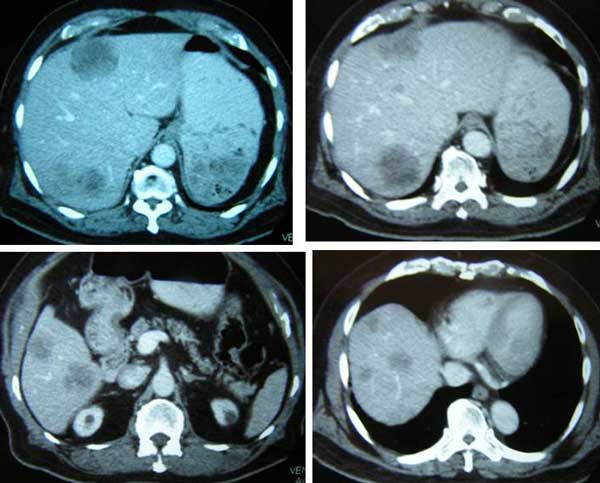

Sometime in April 2012, a 79-old-man came to Penang to seek our help. Let’s refer to him as Peter, a successful professional well known in our Malaysian society. He had cancer of the transverse colon that had spread extensively to his liver. These are his CT scan images.